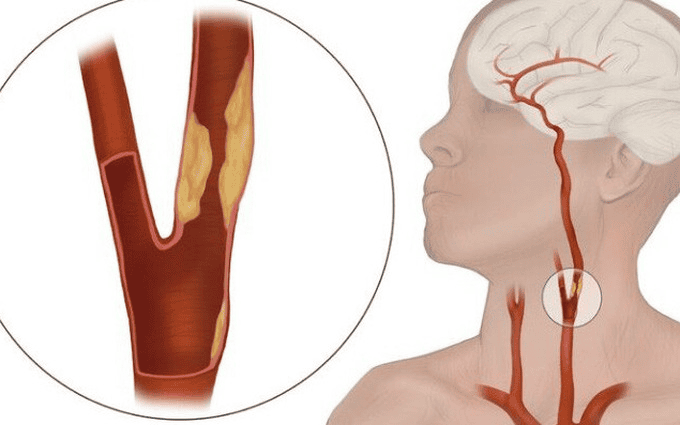

Tiếng chuông cảnh báo từ những triệu chứng bệnh mạch vành mơ hồ Qua trường hợp này, BS.CK1 Nguyễn Đức Chỉnh – Trưởng khoa Nội tổng hợp, Bệnh viện Đa khoa Quốc tế S.I.S Cần Thơ nhận định, những xét nghiệm thông thường như điện tim, siêu âm… rất khó để phát hiện được những trường hợp bệnh mạch vành khi biểu hiện triệu chứng chưa nặng nề. Đôi khi bệnh nhân chỉ có những triệu chứng tương đối mơ hồ như giảm khả năng gắng sức, hụt hơi nên dễ bị bỏ qua. Những bệnh nhân lớn tuổi, có tăng huyết áp, hút thuốc lá, uống rượu bia nhiều năm, rối loạn lipid máu, đái tháo đường… cần lưu ý khi có các triệu chứng mệt khi vận động thông thường, bị hụt hơi, khó thở, tức ngực, nhất là những trường hợp sau đặt stent mạch vành. BS.CK1 Nguyễn Đức Chỉnh cho biết thêm, phương pháp chụp CT Photon hiện nay là tối ưu nhất trong việc loại trừ bệnh động mạch vành nặng giảm được rủi ro dẫn đến nhồi máu cơ tim cấp có thể gây đột tử mà không có triệu chứng báo trước. |

Nhiều người cho rằng chỉ những người thừa cân, béo phì mới cần chú ý đến chế độ ăn để phòng ngừa đột quỵ. Tuy nhiên, thực tế cho thấy người có vóc dáng gầy vẫn có nguy cơ mắc bệnh nếu tồn tại các yếu tố nguy cơ như tăng huyết áp, đái tháo đường, rối loạn mỡ máu, hút thuốc lá hoặc ít vận động. Vì vậy, xây dựng chế độ dinh dưỡng hợp lý là điều cần thiết với tất cả mọi người, không phụ thuộc vào cân nặng.